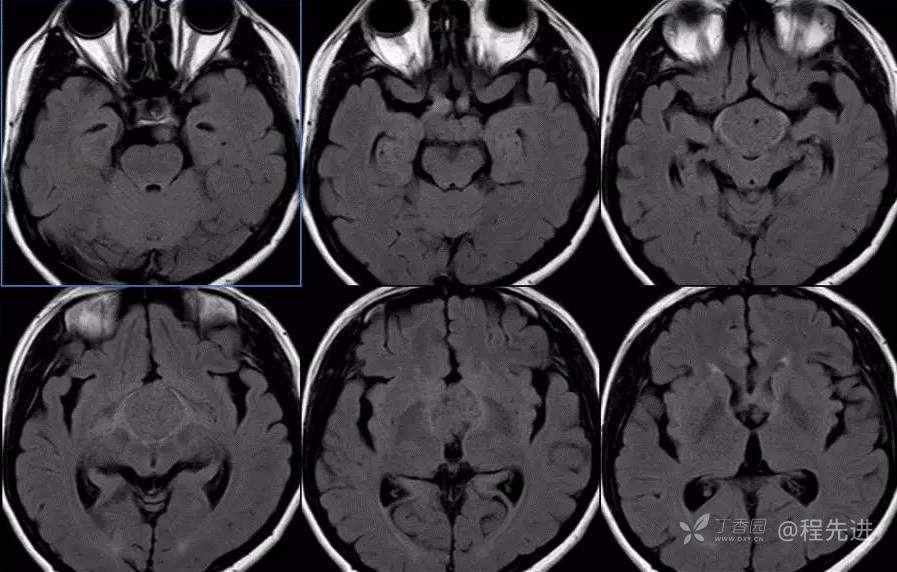

图像依次为T1横断位、T2横断位、T2FLAIR横断位、T2冠状、T1矢状、T1增强横断、矢状、冠状位